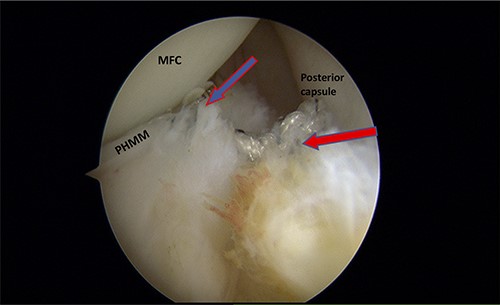

Trans-notch view of the posteromedial compartment of the left knee showing the blue arrow indicates the first lesion at the meniscosynovial junction of the red-red zone, and the red arrow indicates the second tear at the meniscocapsular attachment.

Standard diagnostic arthroscopy confirmed the presence of an intact ACL graft. Trans-notch arthroscopic visualization revealed a double meniscus ramp lesion (Figs 2–5). It was noted that the tear located at the meniscosynovial junction in the red-red zone of the PHMM was associated with MTL disruption, while the second tear was more posteriorly situated at the meniscocapsular junction and was associated with meniscocapsular attachment disruption. Probing of the meniscus resulted in its significant displacement.

Trans-notch view of the posteromedial compartment of the left knee showing the surgical repair of the first tear. The blue arrow indicates the first lesion at the meniscosynovial junction in the red-red zone area. The red arrow shows the second tear at the meniscocapsular attachment. PHMM, posterior horn of the medial meniscus; MFC, medial femoral condyle